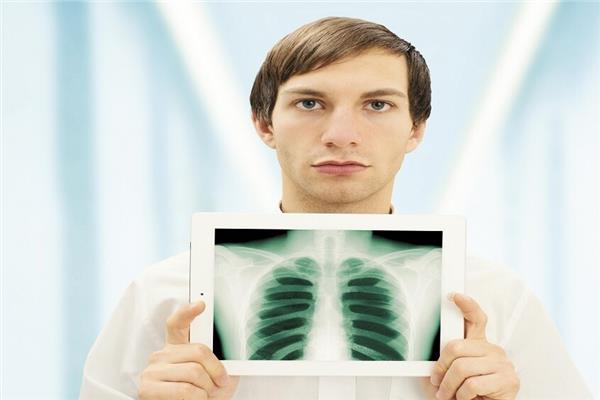

ابتكر علماء معهد موسكو للفيزياء والتكنولوجيا، أول عدسة قادرة على تغيير شدة إشعاع التيراهرتز ديناميكيا، ما يسمح بابتكار تقنيات طبية آمنة قادرة على استبدال الأشعة السينية التقليدية.

وأوضح الباحثون أن موجات التيراهرتز تتمتع بخصائص مميزة في الطيف الكهرومغناطيسي، إذ يمكنها النفاذ عبر المواد غير المعدنية دون أن تُلحق ضررا بالخلايا الحية، مما يجعلها أداة واعدة في التشخيص غير الجراحي وتصوير الهياكل الداخلية للجسم.

واعتمد فريق البحث الروسي على أنابيب الكربون النانوية لصنع عدسة فائقة الرقة ومرنة يمكنها التكيف مع تطبيقات مختلفة، بما في ذلك الأنظمة المحمولة. وتتيح هذه العدسة الجديدة إمكانية تصوير الأورام بدقة عالية، وهو مستوى من الوضوح لم يكن ممكنا تحقيقه في السابق.